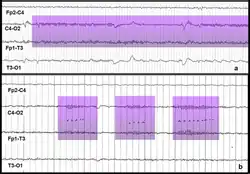

El ritmo mu, también llamado alfa precentral o alfa rolándico,[1] es la «expresión de la actividad eléctrica oscilante que se registra en las zonas motoras centrales del cerebro».[2] Con respecto a las ondas alfa, es similar en frecuencia y amplitud, sin embargo, varía en cuestión de su topografía e importancia a nivel fisiológico.[3] Se mide mediante una electroencefalografía (EEG) y comúnmente oscila entre los ocho y trece Hz.[4]

Un persona suprime los patrones de este ritmo cuando realiza, observa[5] o tiene la intención de realizar una acción motora.[1] No obstante, no se suprime con el hecho de abrir los ojos.[6] Esta supresión es llamada desincronización de la onda debido a que las formas de onda del EEG son producidas por un gran número de neuronas actuando en sincronía. Es por ello que algunos investigadores han sugerido una relación entre el sistema de neuronas especulares y la supresión del ritmo mu.[7]

El ritmo mu es un tipo de onda cerebral medida por medio de una electroencefalografía (EEG). En adultos en reposo y con ojos cerrados, además de predominar las ondas alfa y beta, se observa el ritmo mu que oscila entre los ocho y trece Hz. Predomina en la población joven[4][12] y se limita a breves periodos de entre 0.5 y dos segundos. En personas en reposo, puede registrarse en la corteza sensoriomotora.[7] En infantes, el ritmo mu es detectable desde los cuatro a seis meses de edad y alcanza una frecuencia algunas veces tan baja como 5.4 Hz.[8][14] En un total de 2248 personas, Niedermeyer y Koshino (1975) encontraron una prevalencia de 8.1%. De ellas, considerando los grupos de edad, 9.0% tenían entre 0 y 10 años, 13.8% entre 11 y 20, 8.4% entre 21 y 40 y 4.5% más 41 años.[3]

Aunque es similar en frecuencia a las ondas alfa, varían con respecto a su «morfología, distribución y reactividad». El ritmo mu se localiza en las áreas rolándicas, su ritmo es, en la mayoría de los casos, «unilateral y alternante» y no se modifica al abrir los ojos, pero sí al mover la extremidad contralateral.[12] En este sentido, Kozelka y Pedley (1993) afirman que el ritmo se atenúa con «estímulo táctil o por medio de movimientos pasivos, voluntarios o reflejos». Incluso, agregan, se logra esta respuesta durante la planeación o preparación de los movimientos.[11] El ritmo mu cae dentro de los parámetros normales. No obstante, se ha encontrado una mayor prevalencia dentro de la población con cefalea, trastornos psiquiátricos y otras condiciones.[11] Por otra parte, se piensa que este ritmo puede ser un indicativo del desarrollo de la habilidad de imitar de un infante. Lo anterior cobra importancia debido a que esta habilidad juega un papel importante en el desarrollo de la motricidad, el uso de herramientas y la comprensión de información casual a través de la interacción social.[15]